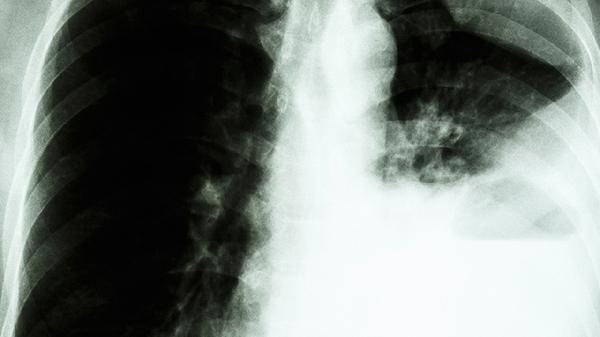

肺部消炎药的选择需根据具体病因和病情决定,常用药物主要有阿莫西林克拉维酸钾片、头孢克肟分散片、左氧氟沙星片、阿奇霉素片、盐酸莫西沙星片等。建议及时就医,在医生指导下规范用药。

肺部感染患者除规范用药外,应保持充足休息,每日饮水1500-2000毫升以稀释痰液。饮食宜清淡,适量补充优质蛋白如鸡蛋、鱼肉,避免辛辣刺激食物。保持室内空气流通,戒烟并远离二手烟环境。出现持续高热、呼吸困难等症状需立即复诊,治疗期间定期复查血常规及胸片评估疗效。抗生素使用须足疗程,不可自行增减药量或停药。